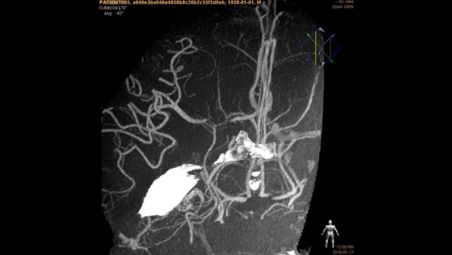

使用静脉内成像作重要决定时需要的信息

VasoCT 静脉内成像的临床优势